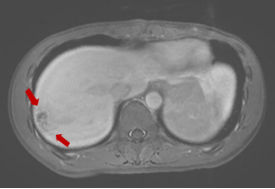

磁共振显示:肝右叶包膜下见多处团片状、楔形病灶,大者位于S7段,范围约2.7cm×1.8cm,部分病灶内见门静脉穿行,门脉血管无阻塞或异常征象,边界欠清。提示:肝右叶包膜下多发异常信号。